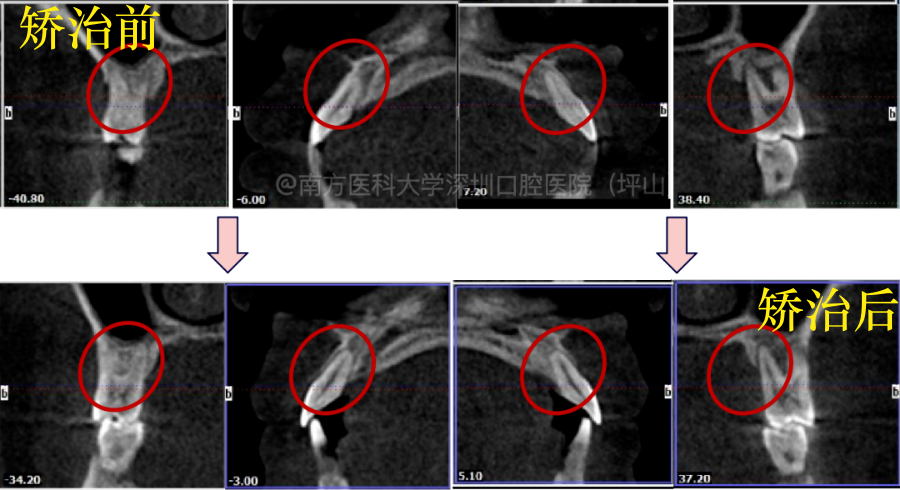

神奇地是,矫正结束后,通过拍摄CBCT检查发现,原本吸收严重的牙槽骨还有明显的新的骨组织生长。说明规范且配合良好的牙周-正畸联合治疗,确实可消除咬合紊乱,促进新骨的沉积,改善牙周炎。

▲牙周正畸联合治疗后,出现牙槽骨再生

▲牙槽骨高度得到部分恢复